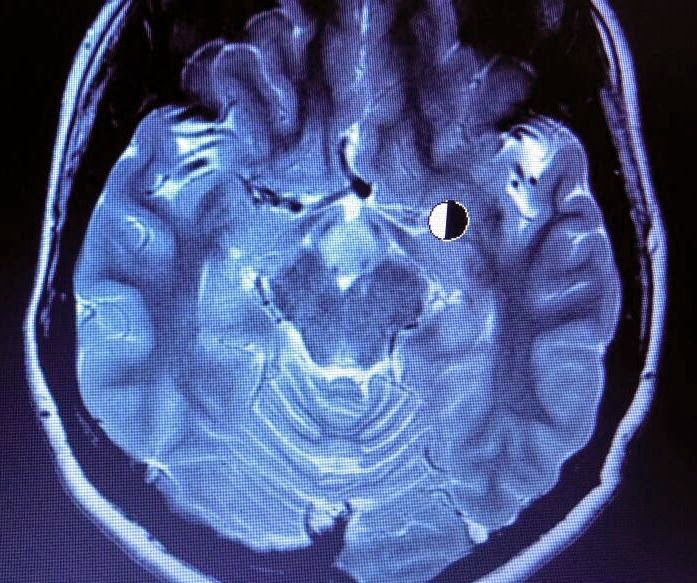

Hypothalamic hamartoma. a, b The coronal a and sagittal b ... 😈

Hypothalamic Hamartoma, MRI Stock Image C030/6379 Science Photo ... 😈

Hypothalamic Hamartoma, MRI Stock Image C030/6377 Science Photo ... 😈

Hypothalamic Hamartoma, MRI Stock Image C030/6380 Science Photo ... 😈

Hypothalamic Hamartoma, MRI Stock Image C030/6382 Science Photo ... 😈

Hypothalamic Hamartoma, MRI Stock Image C030/6383 Science Photo ... 😈

Hypothalamic Hamartoma, MRI Stock Image C030/6381 Science Photo ... 😈

Hypothalamic Hamartoma, MRI Stock Image C030/6384 Science Photo ... 😈

Hypothalamic Hamartoma, MRI Stock Image C030/6385 Science Photo ... 😈